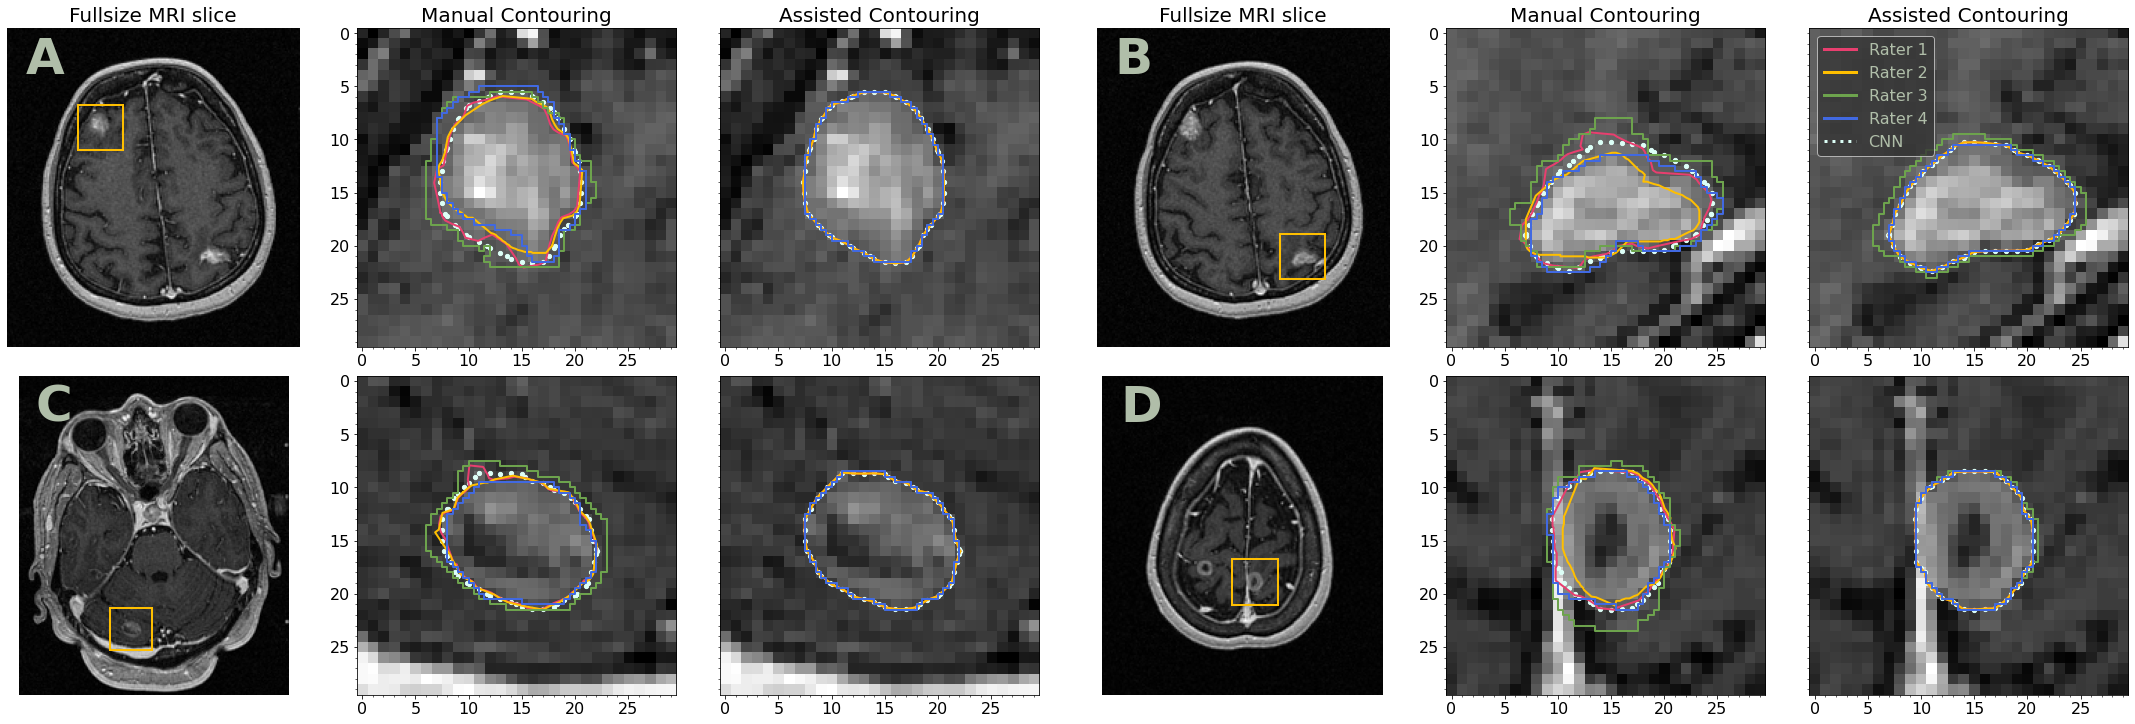

The last row of the Tab. IV gives significant inter-rater contouring agreement improvement when the data for all raters is merged. Agreement is increased from 0.8450.8450.845 (MC) to 0.8710.8710.871 (AC) in terms of median sDSC, median ΔsDSC=0.026ΔsDSC0.026\Delta\text{sDSC}=0.026. Median CCI is increased from 0.7870.7870.787 (MC) to 0.8070.8070.807 (AC), median ΔCCI=0.020ΔCCI0.020\Delta\text{CCI}=0.020. Visual examples of contouring agreement improvement are given in Fig. 5.

Refer to caption

Figure 5: Examples of the metastatic lesions delineated by the raters manually (middle column) and with CNN assistance (right column). The white dotted contours correspond to the CNN’s suggestions. In-plane MRI resolution is 0.9375×0.93750.93750.93750.9375\times 0.9375 mm.